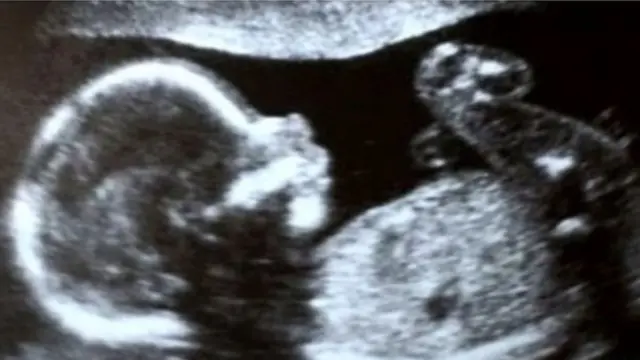

بچی کی شہرت کی وجہ یہ ہے کہ وہ انڈیا ہی نہیں بلکہ ایشیا پیسفک میں یوٹرس یعنی رحم مادر کے ٹرانسپلانٹ سے پیدا ہونے والی پہلی بچی ہے اور گجرات کے بھروچ کی رہنے والی میناکشی ولانڈ پہلی خاتون ہیں جو رحم مادر یا بچہ دانی کے ٹرانسپلانٹ سے ماں بنی ہیں۔

رادھا 22 ہفتوں تک ہی پیٹ میں رہی۔ پیدائش کے وقت اس کا وزن ایک کلو 450 گرام ہی تھا۔ تو کیا رادھا قبل از وقت پیدا ہونے والی بچی ہے اور اسے خصوصی دیکھ بھال کی ضرورت ہے؟